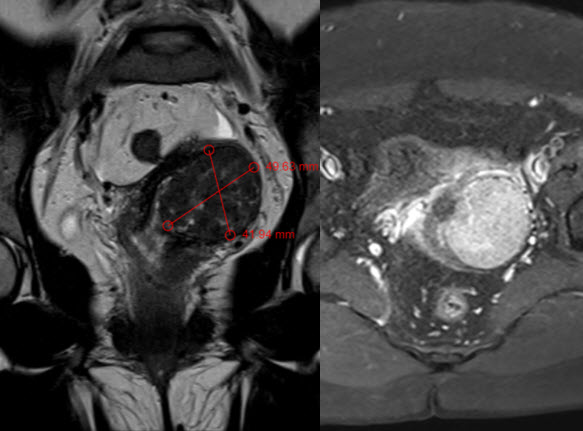

Đầu tháng 9 năm 2019, chị H. đến Bệnh viện Đa khoa tỉnh Quảng Trị khám phụ khoa, bệnh nhân được siêu âm và chụp Cộng hưởng từ 1.5 Tesla được phát hiện có khối u xơ tử cung (UXTC) nằm ở đoạn eo tử cung, kích thước khối u: 41x42x50 mm. Đối với khối u kích thước lớn như thế này nếu điều trị phẫu thuật thì nguy cơ ảnh hưởng đến khả năng làm mẹ sẽ rất cao.

Hình ảnh chụp MRI khối u xơ tử cung lớn

Hình ảnh chụp MRI: khối u xơ tử cung lớn KT: 41x42x50 mm ở đoạn eo tử cung đè ép vào thân tử cung.